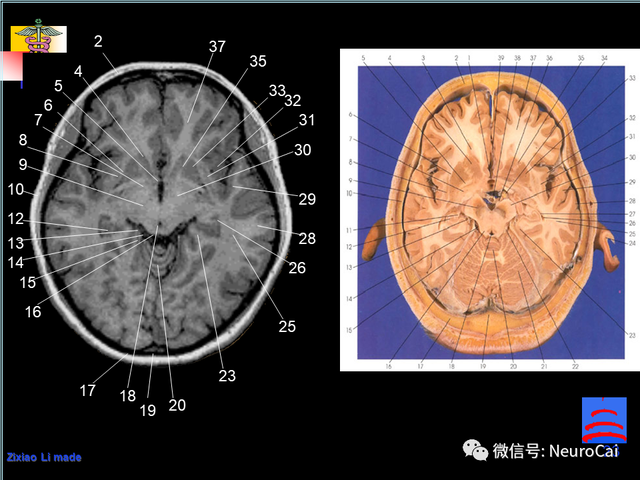

大脑结构图及功能图,人类大脑十大三维解剖图(脑局部解剖与功能图谱)